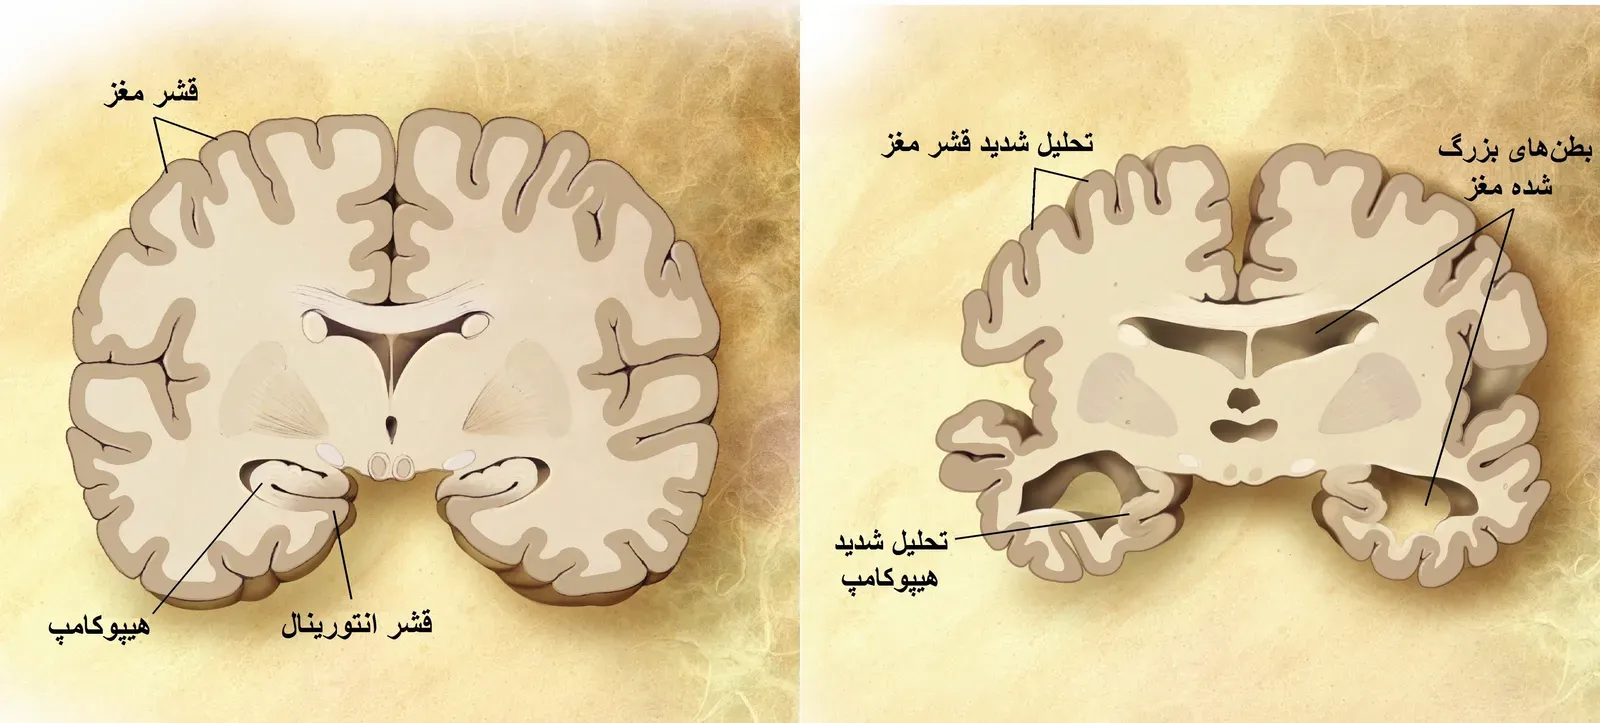

To understand deja vu, it helps to picture memory not as a single filing cabinet but as a network of specialized systems. One part of the brain is especially good at storing the “what, where, and when” of events, while another handles the raw gut-sense that something is familiar. The hippocampus and surrounding medial temporal lobe structures help encode detailed episodic memories, like a birthday party or a first day at work. Meanwhile, regions such as the parahippocampal cortex act more like a familiarity detector, sending a quick yes-or-no signal about whether something has been encountered before. Deja vu appears when this familiarity signal goes rogue.

Most of the time, those systems work together seamlessly, so that a feeling of recognition comes bundled with specific recollection. In a deja vu episode, however, brain imaging and theoretical models suggest that familiarity may flare up alone, without the hippocampus providing the missing details. The result is a strange hybrid state where the brain insists that the scene is known but cannot supply the supporting evidence. Some researchers compare it to an internal quality-control flag, where awareness notices the mismatch and briefly audits its own processes. That internal audit, uncomfortable as it feels, may be one reason why healthy people with intact reality testing experience deja vu as fleeting rather than delusional.